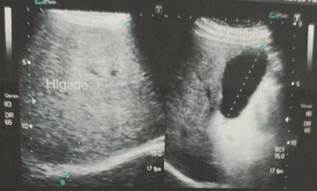

Se realizó exámenes de imagen en donde en la ecografía de abdomen superior se reporta: hígado aumento de ecogenicidad en relación a esteatosis hepática leve, bazo de tamaño y aspecto normal

Figura 3. Ecografía abdominal: hígado aumento de ecogenicidad.

Figura 4. Ecografía abdominal: bazo de tamaño y aspecto normal.